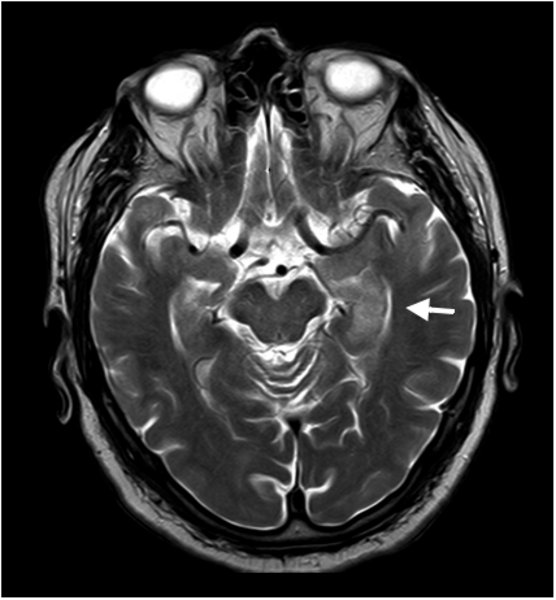

Limbische Enzephalitis

Limbische Enzephalitis - T2

Hyperintensität hippocampal und parahippocampal